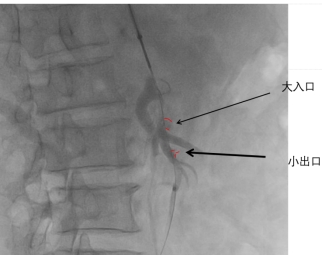

肠系膜上动脉夹层的手术风险高,可能出现术中血管破裂、术后肠道缺血等并发症,在与患者家属充分沟通后,首选腔内介入治疗。经过积极准备,在叶志东主任、樊雪强主任、郑夏医生、贺斌医生的共同努力下,对患者进行了肠系膜上动脉支架联合夹层动脉瘤栓塞治疗。支架释放成功,假腔显影明显减少,肠系膜动脉真腔供血改善,动脉瘤被“封堵”!

术中DSA造影